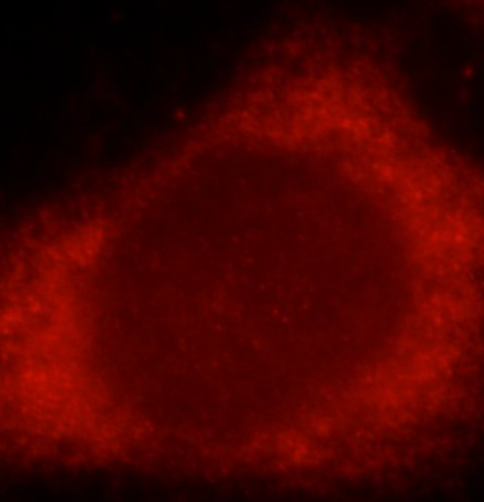

| 验证图片 | Immunohistochemistry of paraffin-embedded human colon cancer tissue slide using FNab07994( SMAD3 Antibody) at dilution of 1:50 Immunofluorescent analysis of HeLa cells using FNab07994 ( SMAD3 Antibody) at dilution of 1:25 and Rhodamine-Goat anti-Rabbit IgG Jurkat cells were subjected to SDS PAGE followed by western blot with FNab07994( SMAD3 Antibody) at dilution of 1:1000 |